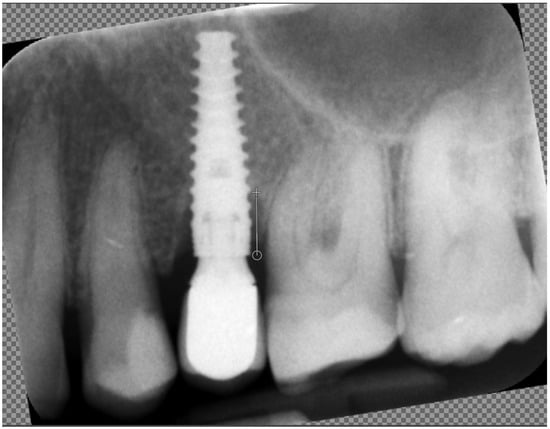

Marginal bone loss (MBL) was measured on radiological images in the standard way: length measured between the platform of the implant and the bottom of the marginal bone loss (Figure 2).

Figure 2. Measuring marginal bone loss on the radiographic images. The white line indicates the implant platform to the bottom of the bone loss cavity.